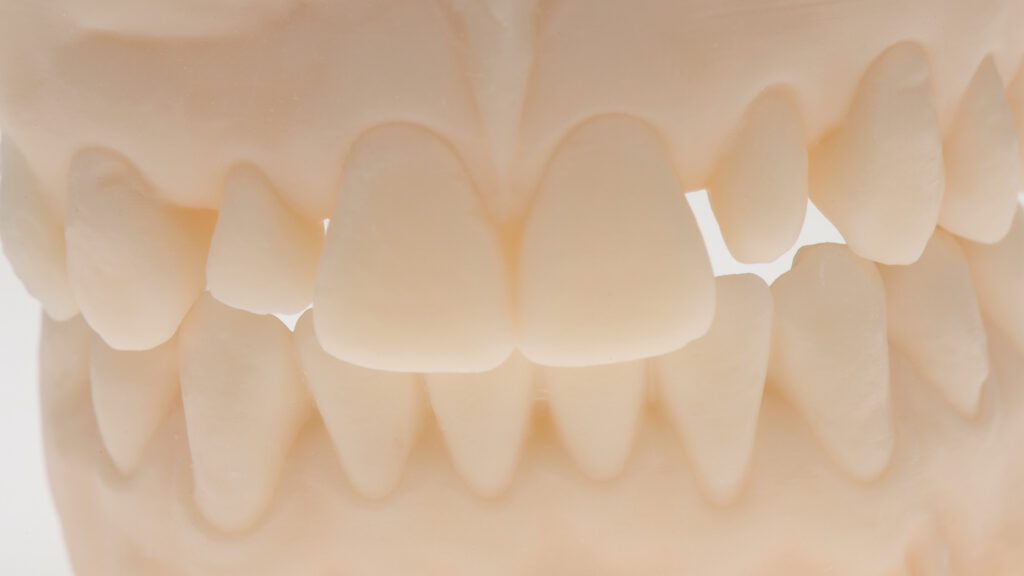

Einer der Vorteile bei der Arbeit mit dem Intraoralscanner ist, dass die digitale Erfassung bei maximaler Okklusion erfolgen kann. Zudem kann die STL-Datei direkt an das Labor übermittelt werden. Die Konstruktion des virtuellen Modells erfolgt mit der Software DTX Studio Design. Anschließend werden die STL-Dateien exportiert und mit einem 3D-Drucker physische Modelle hergestellt (Abb. 5). Um die gescannte Okklusion wiederherstellen zu können, werden die STL-Dateien von Ober- und Unterkiefer getrennt gedruckt. Auf dem Modell wird der Milchzahn regio 12 „extrahiert“ und der periimplantäre Gingivaverlauf ideal gestaltet (Abb. 6 und 7). Höhe und Form des gegenüberliegenden seitlichen Schneidezahns dienen als Vorlage.